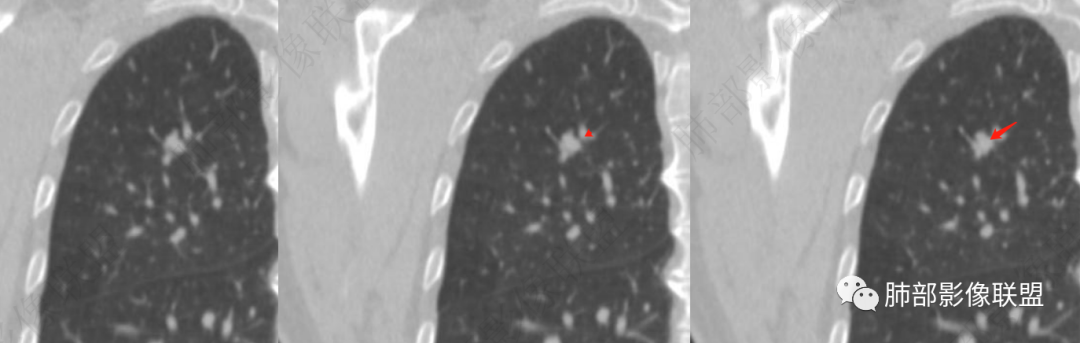

矢状位是这个吗

应该沿病灶长轴建

目前观察到的是:

密度均匀

边缘清楚、光滑,长轴方向较平直

缺点是没看清近端的支气管

4、矢状位示病灶沿肺动脉长轴走形,边缘较平直;